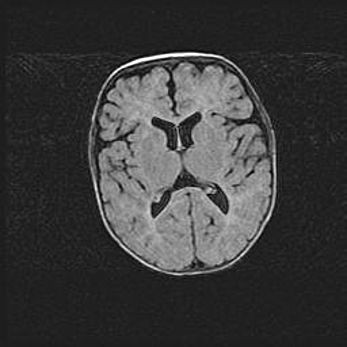

Открытая гидроцефалия.

Возраст: 9 месяцев 12 дней

Вес: 6800 г

Пол: мужской

Окружность головы: 41,5 см

Срок гестации: 28 недель

Гидроцефалия головного мозга у новорожденных имеет характерный признак: опережающий рост окружности головы приводит к визуально хорошо определяемой гидроцефальной форме сильно увеличенного в объёме черепа. Детские неврологи определяют следующие симптомы гидроцефалии у грудничков: выбухающий напряжённый родничок, частое запрокидывание головы, смещение глазных яблок к низу.